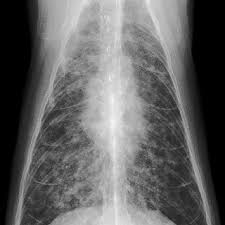

Learning about cancer helps prepare a family to deal with the diagnosis and treatment of their cat. Vets don't know what causes cat lung cancer, but they think pollution might be a causal factor. After adjusting for age, the researchers did find that the cat owners were 15% more likely to have developed lung cancer, but cat owners were also 29% less likely to have contracted endometrial. Cats present with lameness, swelling of the toes and pain The most common primary lung tumour in cats is pulmonary adenocarcinoma, which can arise from the bronchus (the tubes that carry air into the lungs) or from the alveolae (the air sacs).

Once the cancer is diagnosed, staging and grading the cancer can be expensive. Cancer is not just one entity—it is any process of uncontrolled cell growth. Adenocarcinoma grows rapidly and metastasizes to distant parts of the body and organs, including the brain, eyes, bones, and lymph nodes. Yes, cats can get lung cancer. Cats can also have cancer in another part of their body and have it spread to their lungs without ever being exposed to smoke. Learning about cancer helps prepare a family to deal with the diagnosis and treatment of their cat. This mimics the very same type of cancer that humans can develop from asbestos. Primary lung tumors and metastatic lung tumors. Cancer treatment is expensive for both humans and pets. It rapidly grows in the affected cell; One cause of a very specific type of lung cancer called mesothelioma is triggered by asbestos. Cat owners commonly want to know how to recognize if there is fluid in a cat's lung. In fact, research has shown that pet therapy can have often profound benefits during chemotherapy if appropriate precautions are taken.

Pets can be a great source of comfort and companionship during cancer treatment. This mimics the very same type of cancer that humans can develop from asbestos. Hi, i normally hang out on the colorectal cancer board, but my cancer has spread to my lungs, so i wanted to share what i found out about cat litters, because i decided to find the best litter to avoid inhaling the dust that all the popular clay clumping litters can cause. It rapidly grows in the affected cell; With the advent of virus testing, vaccination against felv and selective breeding, the cancer caused by this virus has diminished greatly. Squamous cell carcinoma and bronchioalveolar carcinoma are other types of cancer that occur in cat lungs. Those that do may have difficulty breathing (labored or rapid breathing, even while resting), reduced ability to manage walks (exercise intolerance), decreased appetite, weight loss, coughing or sneezing (with or without discharge. The medical term for the accumulation of fluid in the lungs is pulmonary edema. Common cancers with the potential to spread to the lungs include oral, mammary. Feline lung cancer causes and symptoms Although cats are less prone to developing primary lung cancer than dogs, the reported incidence has increased during the last 20 years. Create a comfortable environment for a cat with cancer some cats with cancer will have less energy and become less active. The disease can develop in cats of any age;

However, lung cancer in cats has been linked to smoking environments and cats exposed to smoke. My cat has a tumor in her lung, and has spread to her toes in one paw. Attaches itself to the tissue under the skin in that area; Feline lung cancer causes and symptoms Lymphoma typically happens in older felines and most commonly occurs in the small intestines, says dr. Hi, i normally hang out on the colorectal cancer board, but my cancer has spread to my lungs, so i wanted to share what i found out about cat litters, because i decided to find the best litter to avoid inhaling the dust that all the popular clay clumping litters can cause. It is caused by uncontrolled cell growth, and affects a wide range of cell types and organs in the body. After adjusting for age, the researchers did find that the cat owners were 15% more likely to have developed lung cancer, but cat owners were also 29% less likely to have contracted endometrial. Vets don't know what causes cat lung cancer, but they think pollution might be a causal factor. Lung adenocarcinoma in cats adenocarcinoma is a malignant neoplasm, making up about 75 percent of all primary lung tumors in cats. Cancer is much more likely to develop in a cat that has reached her golden years, but even young cats can develop this condition. About 20 to 30 years ago, this virus led to cancer development in young cats (2 to 5 years old). Unlike humans, they cannot open windows or go outside to escape it.